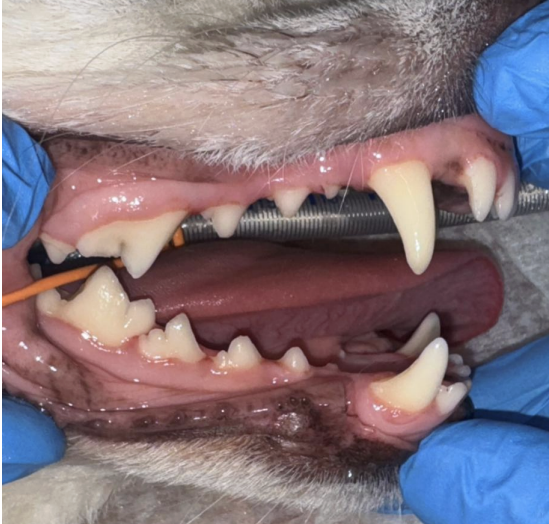

・Before

歯石の沈着と口臭を気にされていました。

歯磨きも挑戦されているようですが、うまく磨けず歯石がついている状態でした。

特に奥歯に歯石がついており、一部赤みや腫れている部分も認められました。